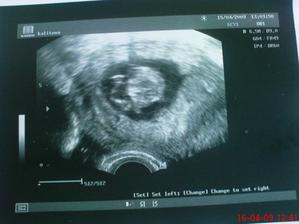

* 31.3. kontrola OK, mimi kopalo nožičkou a mávalo rukama. Byla jsem úplně hotová a když se mimčo pohlo tak jsem úplně vykřikla. Paní doktorka se smála a udělala nám fotku. Dle utz 8+6tt